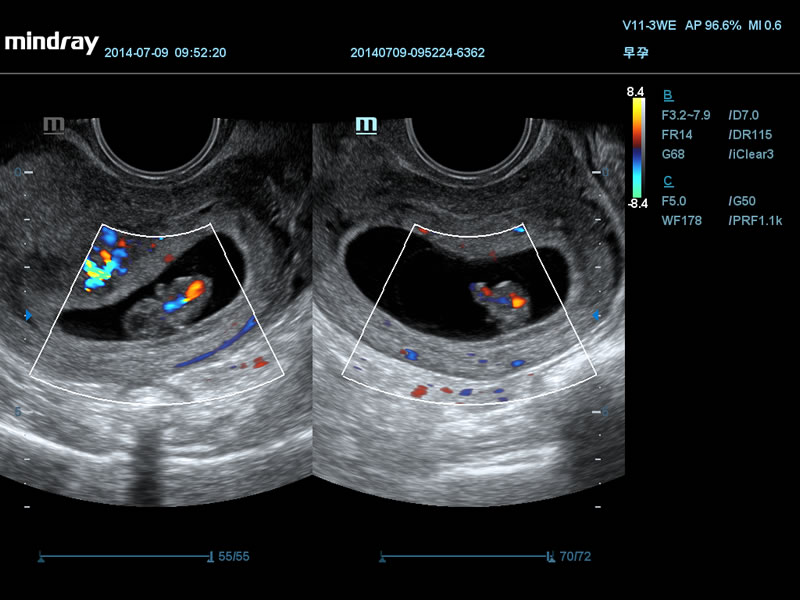

2 представления одного плодного мешка, Single CRL

Сердце эмбриона

Сброс крови через овальное окно